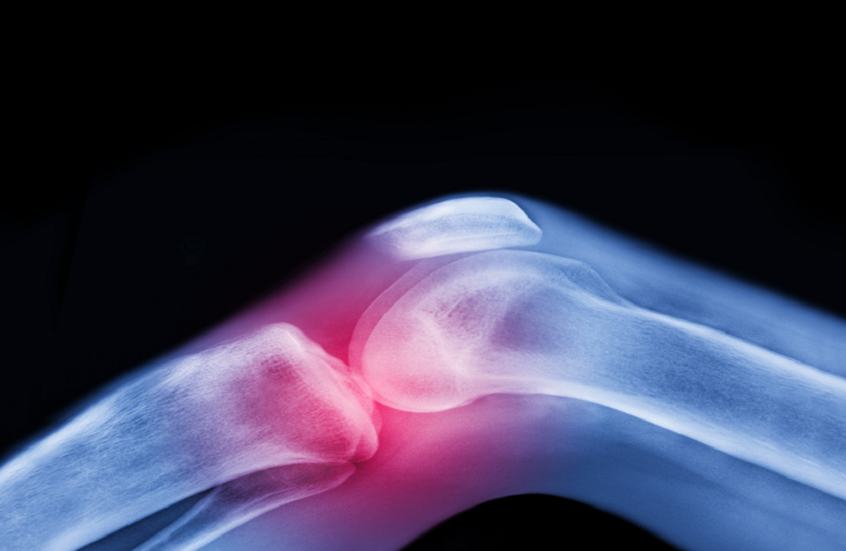

تعتبر آلام المفاصل وتيبّس الركبتين وأوجاع الوركين من الشكاوى الشائعة بين كبار السن، وغالبا ما يُقبل بها كجزء طبيعي من أعراض الشيخوخة.

لكن الواقع الطبي يوضح أن هذا ليس مصيرا حتميا، فالفصال العظمي — أكثر أمراض المفاصل شيوعا في العالم — يمكن الوقاية منه وعلاجه بطرق غير دوائية فعّالة للغاية.